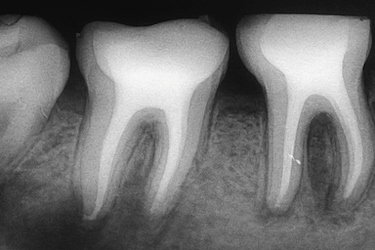

La endodoncia puede variar según el tipo de diente, ya que no todas las piezas tienen el mismo número de raíces ni de conductos. Algunas tienen una sola raíz, otras dos y los molares tres o más.

Por eso distinguimos entre endodoncias unirradiculares, birradiculares y multirradiculares, según su complejidad.

Endodoncia multirradicular

Este tipo de endodoncia se realiza en dientes con más de dos conductos. Los molares superiores son el mejor ejemplo.

Los molares, especialmente los superiores, pueden tener tres o incluso cuatro raíces. En estas piezas el tratamiento endodóntico es más complejo. Con técnicas rotatorias y radiografías digitales, el especialista puede acceder y tratar todos los conductos con precisión.